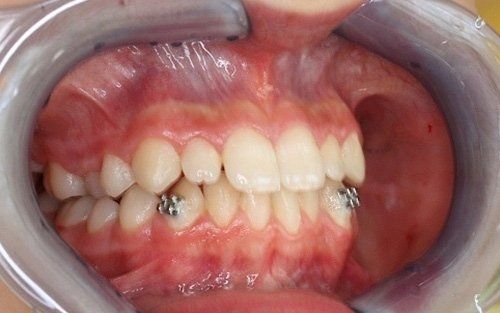

ORTODONZIA CLASSICA

Tramite brackets, ovvero attacchi (metallici, in resina o in ceramica) posizionati sui denti, viene realizzata una metodica fissa, con lo scopo di riallineare gli elementi dentari presenti in arcata raggiungendo la migliore occlusione possibile. L’opportunità di utilizzare una o l’altra tecnica, o una combinazione delle stesse dipende dalla diagnosi effettuata mediante le registrazioni iniziali.